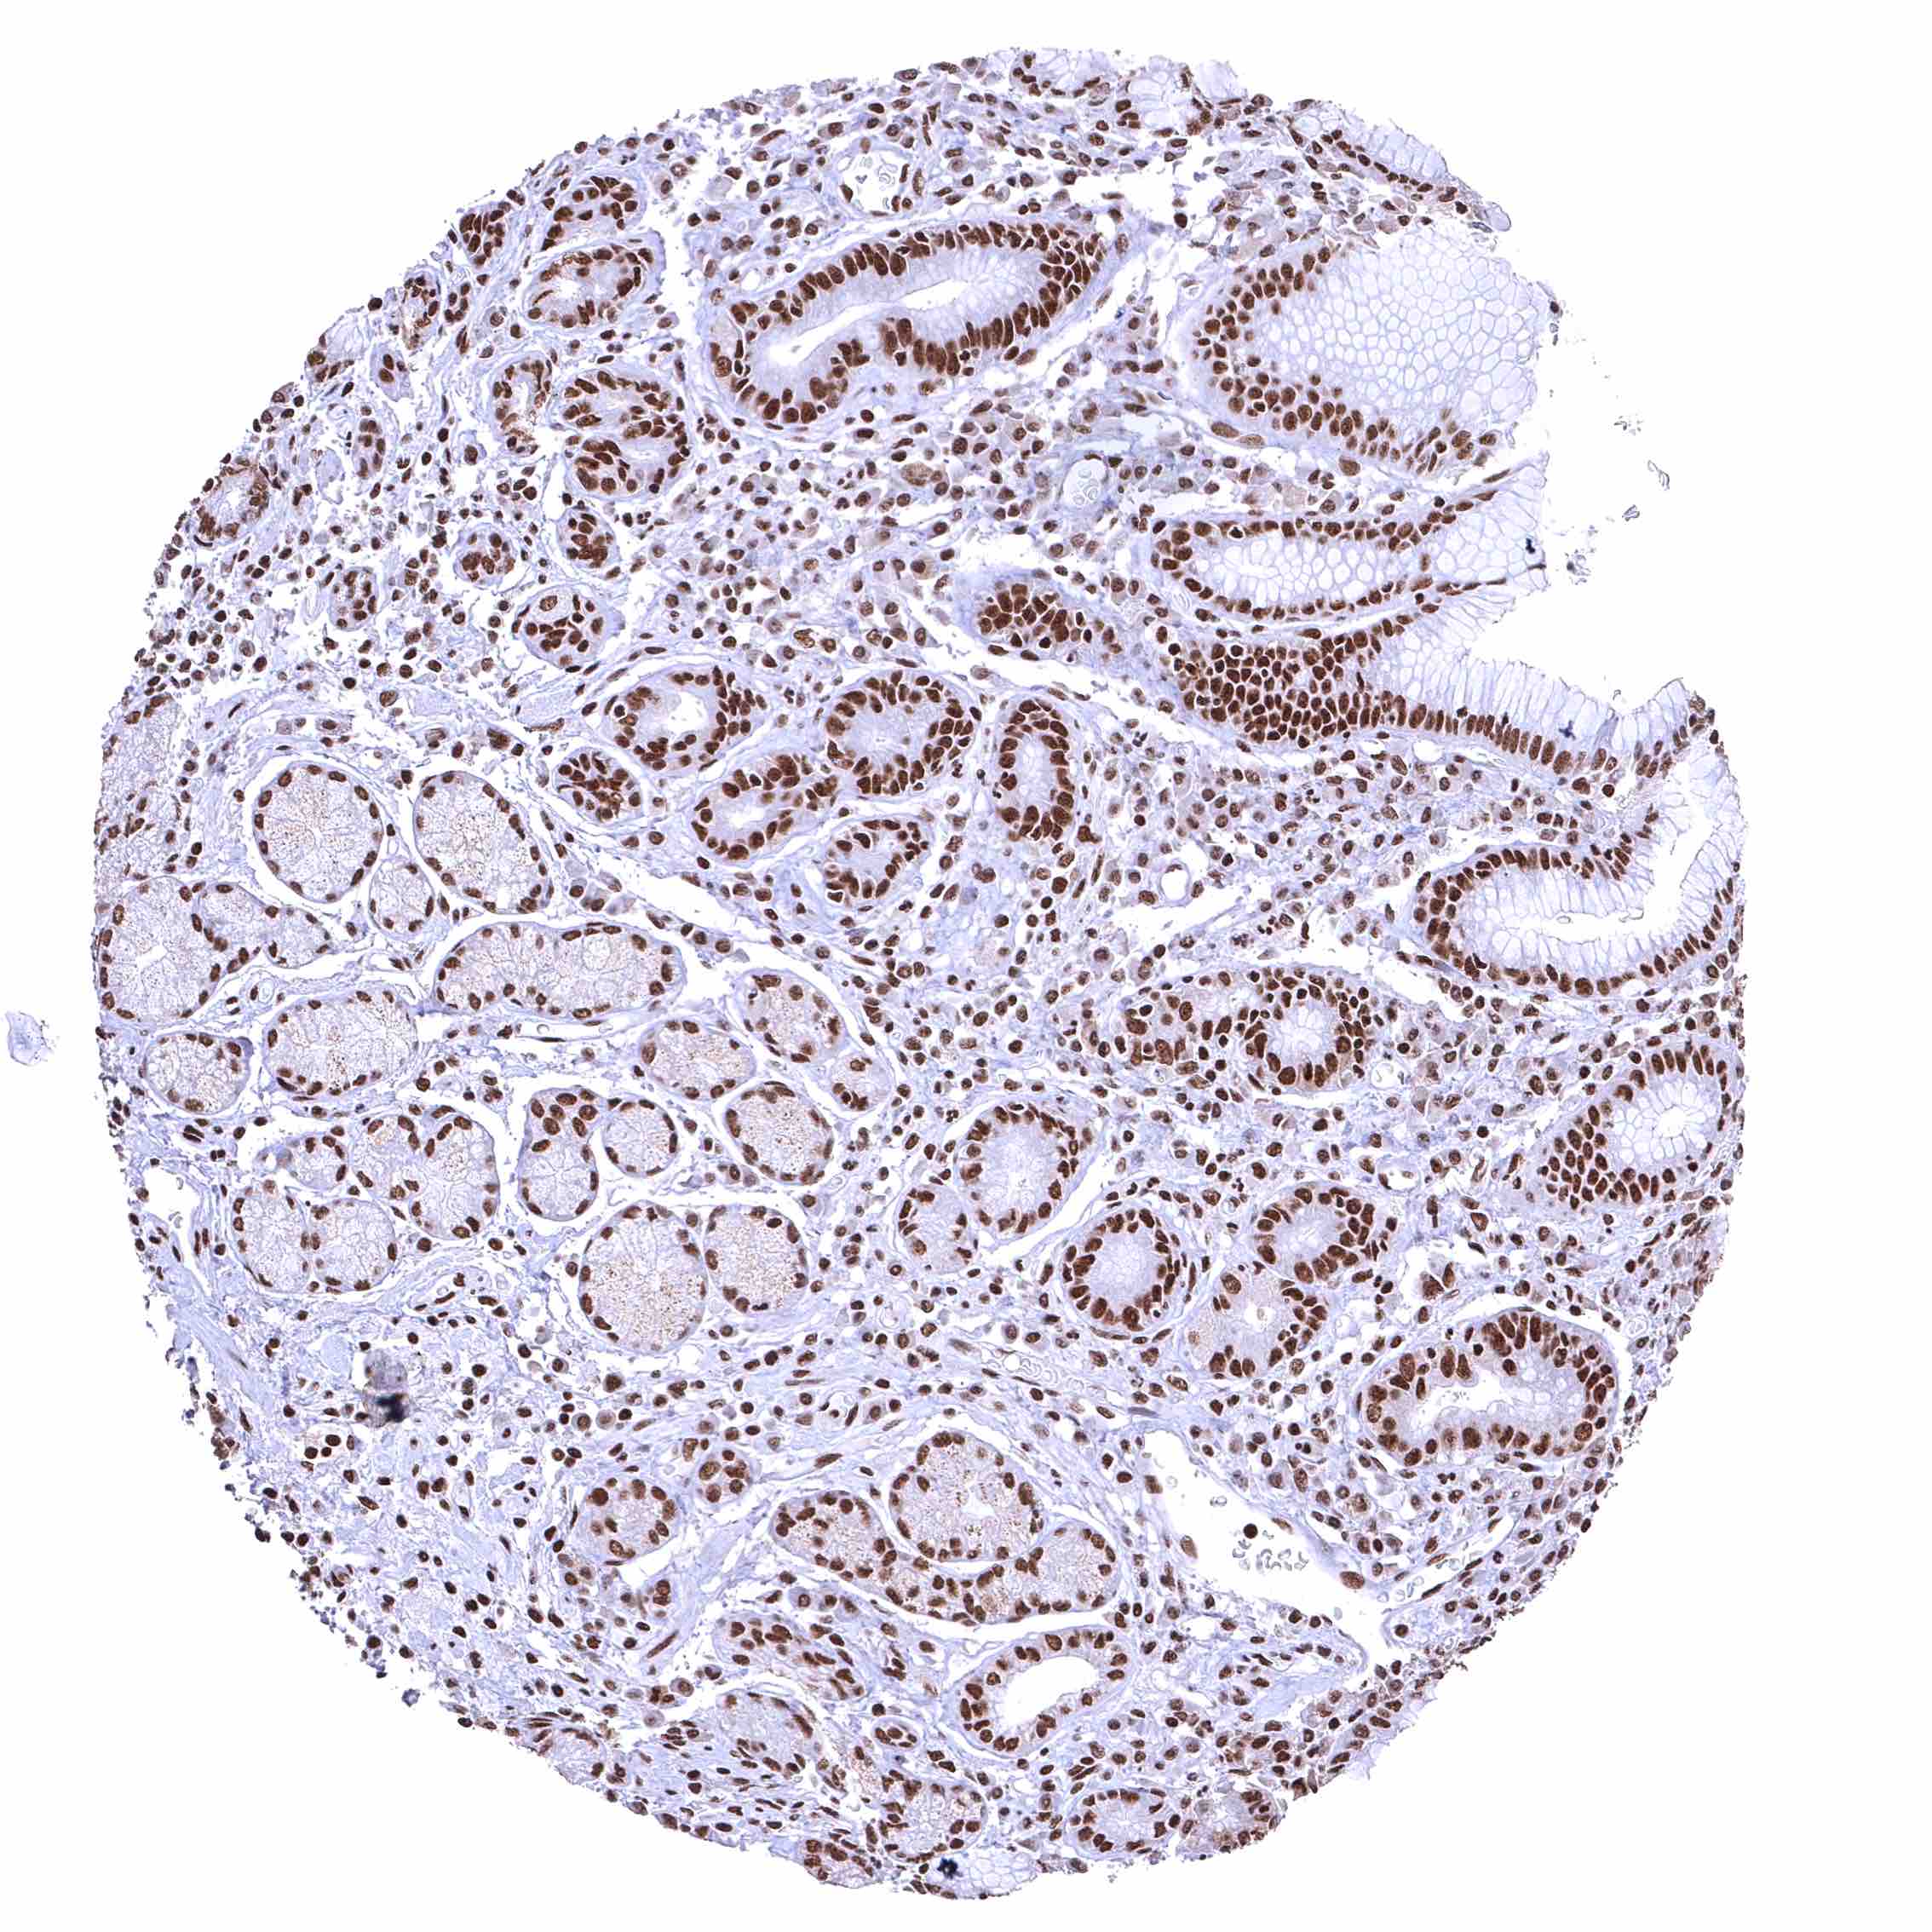

Colon descendens, mucosa – Nuclear BRD4 staining of surface epithelial cells is weaker than in crypts.

Rectum, mucosa – Nuclear BRD4 staining of surface epithelial cells is weaker than in crypts.